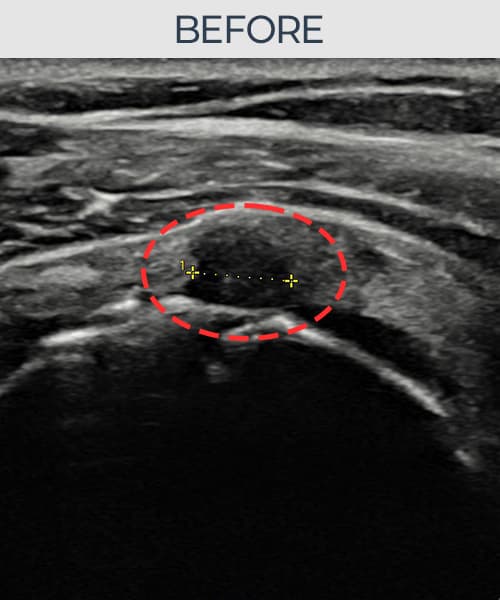

右侧 冈上肌腱 石灰化肌腱炎

14mm × 10mm